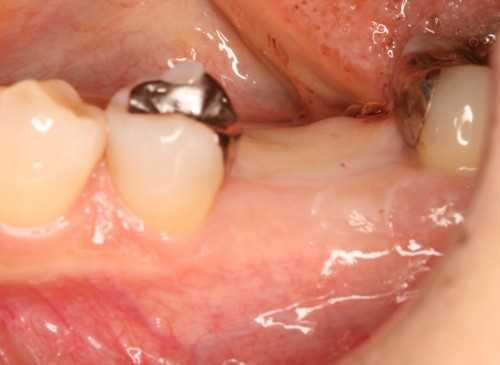

被せ物装着